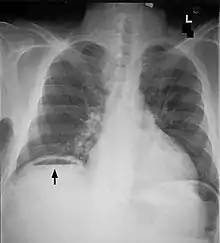

Frontal chest X-ray. The air bubble below the right hemidiaphragm (on the left of the image) is a pneumoperitoneum.

Pneumoperitoneum is pneumatosis (abnormal presence of air or other gas) in the peritoneal cavity, a potential space within the abdominal cavity. The most common cause is a perforated abdominal organ, generally from a perforated peptic ulcer, although any part of the bowel may perforate from a benign ulcer, tumor or abdominal trauma. A perforated appendix seldom causes a pneumoperitoneum.

When present, pneumoperitoneum can often be seen on projectional radiography, but small amounts are often missed, and CT scan is nowadays regarded as a criterion standard in the assessment of a pneumoperitoneum.[18] CT can visualize quantities as small as 5 cm³ of air or gas.